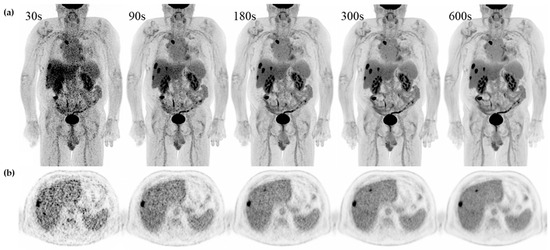

One patient out of 50 had a 30 mm rather than 60 mm VOI placed in the right liver lobe due to wide-spread disease and major vessels. Image noise computed as COV was closest to current acceptable values for standard of care after 90 s on the Vision Quadra (COVmean = 0.14). Therefore, 90 s acquisition was implemented as the reference acquisition for current clinical standard in PET/CT in this study. As expected, COV improved significantly with increasing acquisition time across all time points (PB < 0.001). Axial slices and MIP as viewed by observers in the qualitative evaluation can be seen in Figure 3.

Figure 4. Examples of a single set of scans across acquisition times in a 71 y male referred for recurrent hepatic cancer. (a) Maximum intensity projection (MIP) and (b) axial slice with simultaneous display of liver, ventricle, and spleen from 30 s, 90 s, 180 s, 300 s, and 600 s from the same patient.